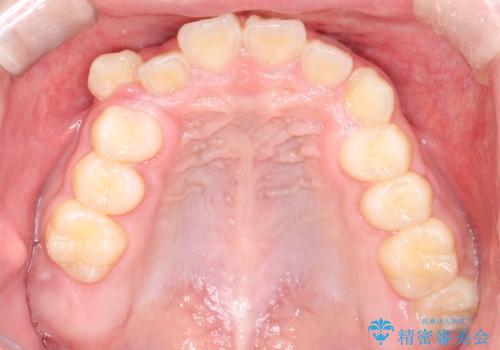

八重歯・歯並びのデコボコとディープバイトを改善した抜歯ワイヤー矯正症例

- 八重歯と咬み合わせを治したいを主訴にご来院された患者様です。

矯正の精密検査の結果上顎左右4番の計2本を抜歯し、審美性に配慮したワイヤー矯正装置(審美装置)を用いて治療を行いました。

八重歯などの歯列のデコボコが綺麗に改善され、患者様にも大変喜んでいただけました。また、咬み合わせが深い「ディープバイト」も併せて改善し、見た目だけでなく機能面でもバランスの取れた咬合を獲得しています。